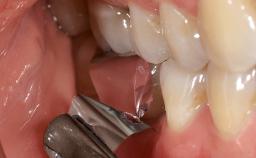

Peri-Implantitis Modified by the Presence of Submucosal Excess Cement: Reconstructive Therapy and a Ten-Year Follow-up

This case outlines the reconstructive therapy by Giovanni Salvi resulting in defect fill and inflammation-free peri-implant soft tissues at 10-year follow up. This case highlights the importance of regular monitoring of implants during supportive therapy.

A 30-year-old female patient was referred to the Department of Periodontology of the University of Bern, Switzerland, by a private dentist. Tooth 45 was congenitally missing and had been replaced with an implant three years prior to the first visit at the Department of Periodontology.